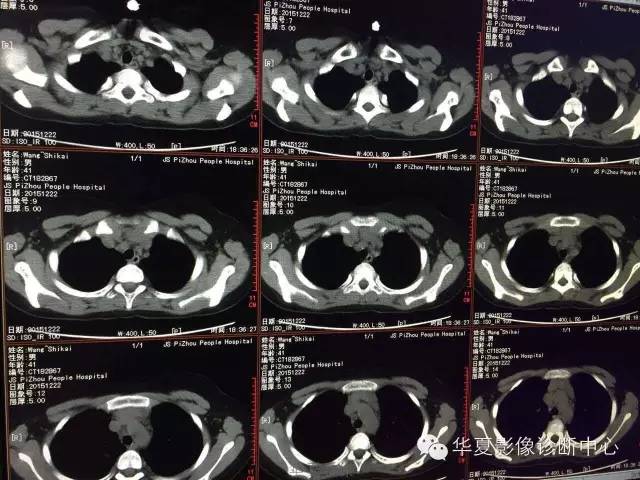

支原体肺炎1例CT影像表现